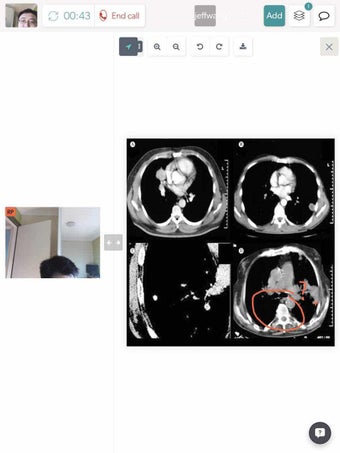

COVIU - это бесплатное приложение для Android, которое предоставляет платформу для видео-сотрудничества. Это приложение предлагает простой и интуитивно понятный интерфейс, который позволяет всем делиться и аннотировать файлы, доски или свой экран. Это отличный инструмент для членов команды, партнеров и клиентов.

Одной из самых впечатляющих особенностей COVIU является его передовое шифрование для обеспечения безопасности и производительности. С COVIU вы можете быть уверены, что ваши видеозвонки защищены и ваши данные защищены. Кроме того, приложение обеспечивает четкое видео и аудио с использованием уже имеющегося оборудования.